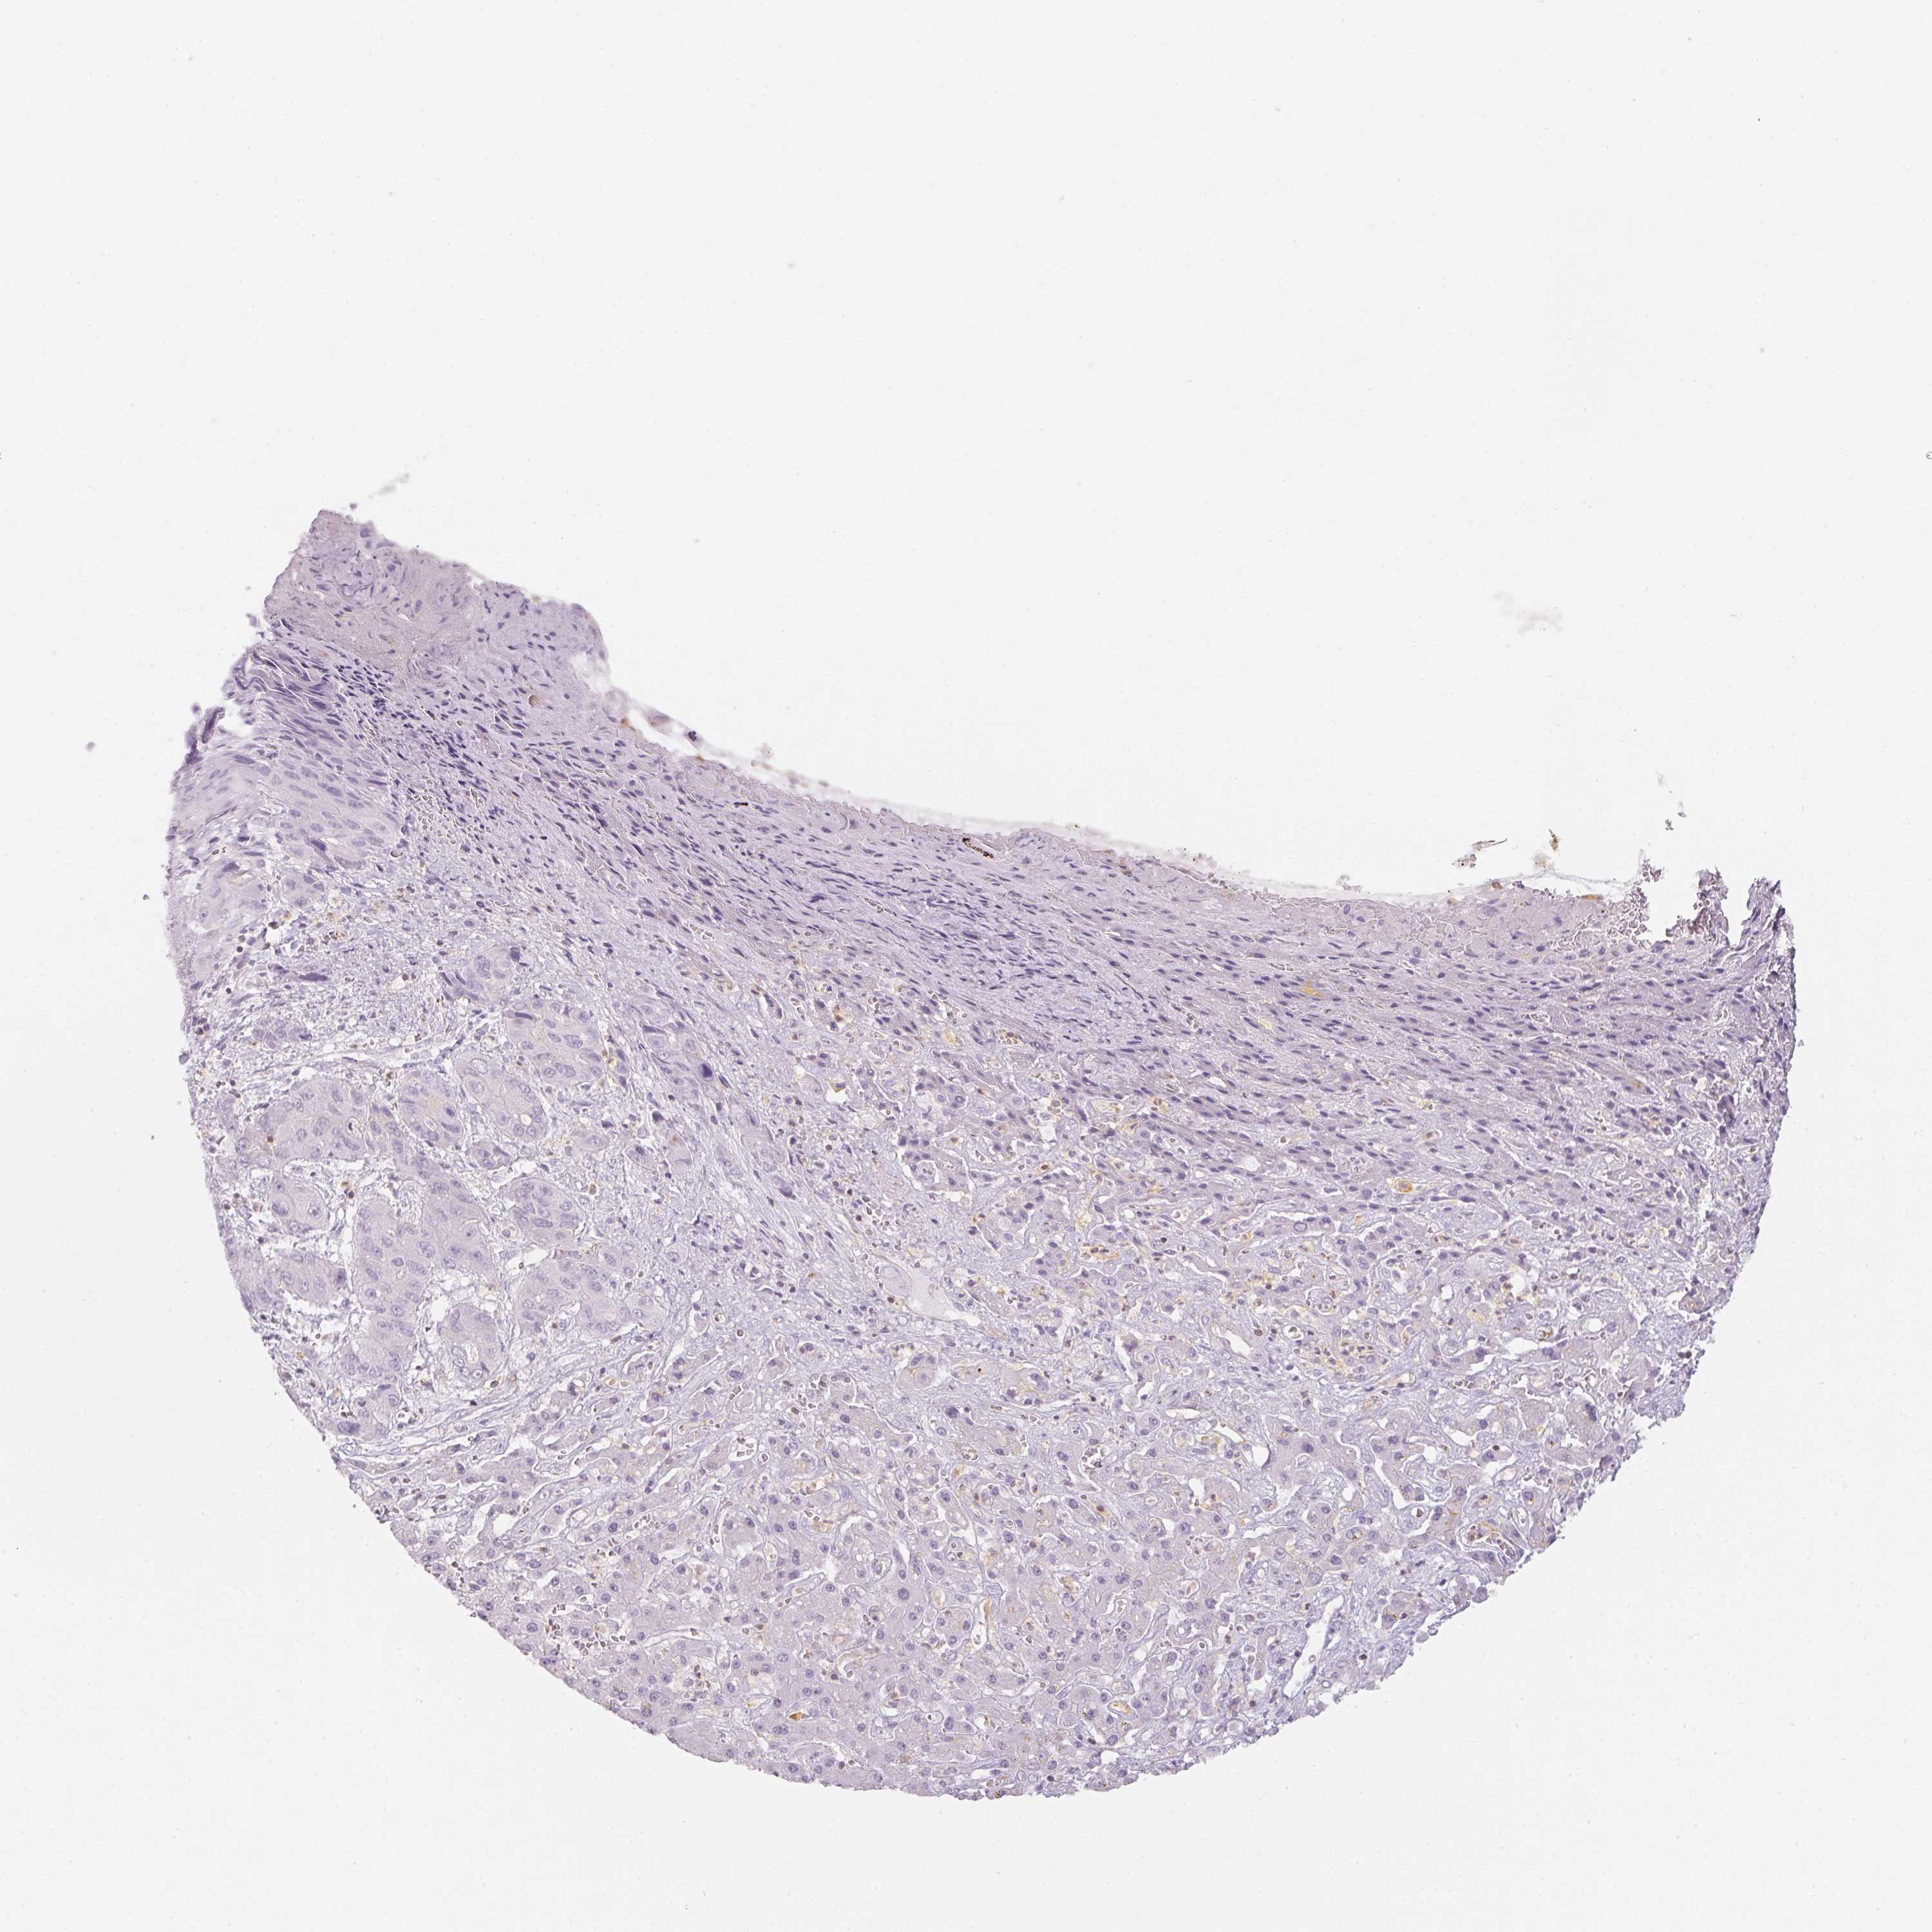

LIVER CANCER - Protein expressioni

A mouse-over function shows sample information and annotation data. Click on an image to view it in a full screen mode. Samples can be filtered based on level of antibody staining by selecting one or several of the following categories: high, medium, low and not detected. The assay and annotation is described here.

Note that samples used for immunohistochemistry by the Human Protein Atlas do not correspond to samples in the TCGA dataset.

Antibody stainingi

Antibody staining in the annotated cell types in the current human tissue is reported as not detected, low, medium, or high, based on conventional immunohistochemistry profiling in selected tissues. This score is based on the combination of the staining intensity and fraction of stained cells.

Each image is clickable and will lead to virtual microscopy that enables deeper exploration of all samples and also displays staining intensity scores, fraction scores and subcellular localization as well as patient and tissue information for each sample.

Antibody HPA052569

Staining

High

Medium

Low

Not detected

Intensity

Strong

Moderate

Weak

Negative

Quantity

>75%

75%-25%

<25%

None

Location

Nuclear

Cytoplasmic/membranous

Cytoplasmic/membranous,nuclear

Carcinoma, Hepatocellular, NOS

Cholangiocarcinoma